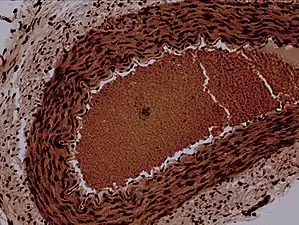

Rabbit arteriole at 100X | |

Arterioles have muscular walls (usually only one to two layers of smooth muscle cells) and are the primary site of vascular resistance. The greatest change in blood pressure and velocity of blood flow occurs at the transition of arterioles to capillaries. This function is extremely important because it prevents the thin, one-layer capillaries from exploding upon pressure. The arterioles achieve this decrease in pressure, as they are the site with the highest resistance (a large contributor to total peripheral resistance) which translates to a large decrease in the pressure.[2]

In a healthy vascular system the endothelium lines all blood-contacting surfaces, including arteries, arterioles, veins, venules, capillaries, and heart chambers. This healthy condition is promoted by the ample production of nitric oxide by the endothelium, which requires a biochemical reaction regulated by a complex balance of polyphenols, various nitric oxide synthase enzymes and L-arginine. In addition there is direct electrical and chemical communication via gap junctions between the endothelial cells and the vascular smooth muscle.

Blood pressure in the arteries supplying the body is a result of the work needed to pump the cardiac output (the flow of blood pumped by the heart) through the vascular resistance, sometimes termed total peripheral resistance. An increase in the tunica media to luminal diameter ratio has been observed in hypertensive arterioles (arteriolosclerosis) as the vascular wall thickens and/or luminal diameter decreases.